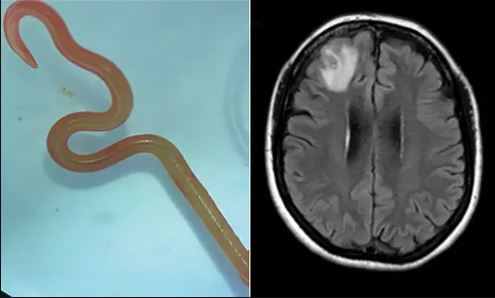

Για πρώτη φορά στα χρονικά της ιατρικής, ένα σκουλήκι που κανονικά παρασιτεί σε πύθωνες αφαιρέθηκε ζωντανό από τον εγκέφαλο μιας άτυχης γυναίκας στην Αυστραλία.

ο δρ Χάρι Πρίγια Μπάντι, ο νευροχειρουργός που αφαίρεσε το σκουλήκι, μήκους 8 εκατοστών.

Το παράσιτο, του είδους Ophidascaris robertsi, ανήκει στην ομάδα των ασκαρίδων, σκουληκιών που ζουν στο πεπτικό σύστημα πολλών σπονδυλωτών ζώων συμπεριλαμβανομένου του ανθρώπου.

Μέχρι σήμερα όμως το συγκεκριμένο είδος είχε βρεθεί αποκλειστικά σε ένα είδος αυστραλιανού πύθωνα.

όμως είχαν εμφανιστεί νέα, όπως δυσκολία στη μνήμη και κατάθλιψη. Η μαγνητική τομογραφία αποκάλυψε τότε μια περίεργη κηλίδα στον δεξιό μετωπικό λοβό του εγκεφάλου.

Όταν οι γιατροί κατάλαβαν ότι επρόκειτο για παράσιτο, το αφαίρεσαν στο χειρουργείο και το έστειλαν σε παρασιτολόγους, οι οποίοι ταυτοποίησαν το είδος του σκουληκιού με μοριακά τεστ και μορφολογικές εξε

τάσεις

.